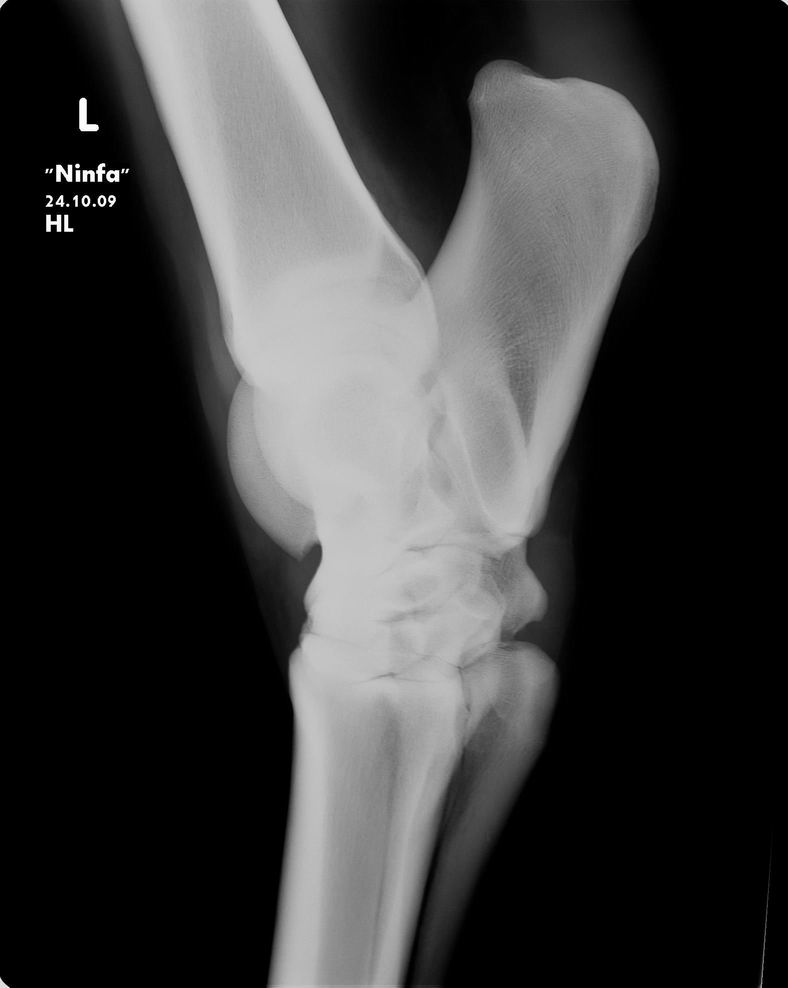

Posted on Monday, Nov 16, 2009 - 4:55 pm: Dear Dr O,I can give you for now some radiographs of the mare. She is not on bute, she is not a riding horse, just on the pasture. For the moment she is walking better after my last trim (left the complete heel) Next week I can give you more exterior pictures of the mare. Tom ![]() ![]() ![]()

Posted on Tuesday, Nov 17, 2009 - 7:09 am: Hello cavalonatural,I am trying to figure out what questions you have about these radiographs. Though I do not do radiographic interpretations from standard resolution internet images there is not much to say about these other than they are incomplete studies of the regions studied. There is not enough of the hoof to really help us though there is an impression of adequate sole, but I can't be certain since the bottoms are cut off. Concerning whether and how to shoe, when we can see the hooves and how well balanced they appear I think we will be able to help more. Be sure the images are taken with the horse standing square. DrO |